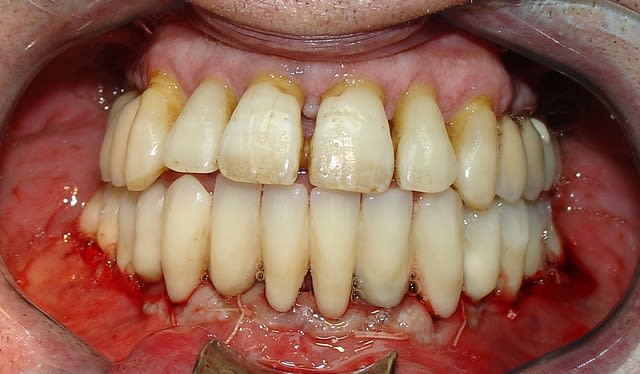

Quand je fais des EMCI totale sur 6 à 8 implants avec appui osseux

je pose les implants puis les piliers qui sont l’équivalent de couronnes télescopiques, et le bridge à armature métallique sans scellement ni vis, dans la même séance

le côté positif, de la chir guidée: implant posé, moignon définitif posé et prothèse provisoire (je devrais dire transitoire...;-)) vraiment esthétique et bien adaptée posée dans la même séance...amha un vrai plus pour une parfaite cicatrisation...si je me souviens bien tu es déjà un partisan du moignon définitif posé dans la séance...la chir guidée permet d'aller au bout de ce concept...

c'est difficile d'expliquer, et tellement plus simple à montrer, mais oui, c'est totalement passif et en quelque sorte à géométrie variable car les piliers provisoire sont scellés dans l'intrados de la prothèse lors de la chirurgie...